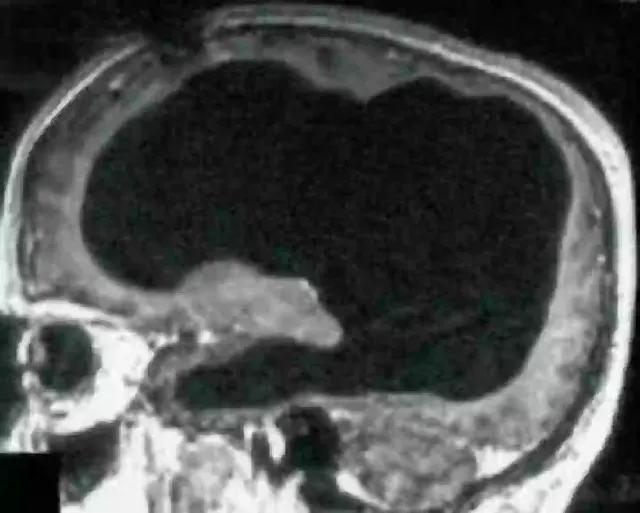

Tudo começou quando ele foi ao médico por causa de uma leve dor e fraqueza na perna, que persistiu por duas semanas. O sintoma parecia comum, mas os exames revelaram algo chocante: seu crânio estava quase completamente cheio de líquido, deixando apenas uma fina camada de tecido cerebral. A condição, chamada hidrocefalia, ocorre quando o acúmulo de líquido cefalorraquidiano comprime o cérebro. No caso dele, esse processo destruiu gradualmente cerca de 50% do órgão ao longo de 30 anos.

A história tem um detalhe ainda mais curioso: o homem foi diagnosticado com hidrocefalia ainda bebê e recebeu um stent para drenar o excesso de líquido. Aos 14 anos, o dispositivo foi removido e, a partir de então, o cérebro começou a ser silenciosamente "corroído". Durante décadas, ele não sentiu nada além de dores passageiras, como a que o levou ao hospital.

O caso desafia as noções tradicionais sobre a relação entre a estrutura do cérebro e a consciência. Durante anos, os cientistas associaram funções específicas a áreas do cérebro, como a fala no lobo frontal ou a visão no occipital. Mas quando metade do órgão desaparece, como explicar a manutenção de habilidades básicas e até complexas?

Uma hipótese é que o cérebro adulto tem uma plasticidade maior do que imaginávamos. Em resposta a lesões ou danos prolongados, outras regiões podem assumir funções das áreas afetadas. No caso do francês, é possível que o tecido remanescente tenha se reorganizado para compensar a perda, garantindo funções essenciais.

Isso também levanta questões sobre a natureza da consciência. Alguns teóricos argumentam que não está ligado a uma região específica, mas surge da interação entre diferentes partes do cérebro. Se uma grande parte do órgão é substituída por fluido, como a consciência persiste? O caso sugere que a mente humana pode ser mais resiliente e adaptável do que supomos.